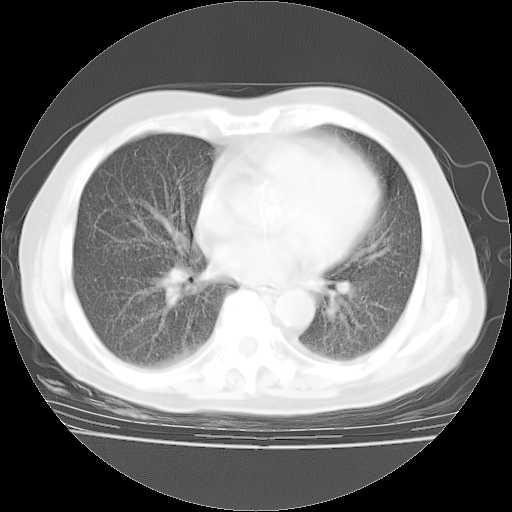

4月28日肺部CT——再次出现类似去年5月9日——透光度降低,“间质性”改变。

4月28日肺部CT——再次出现类似去年5月9日——磨玻璃样、间有“粟粒样”改变。

4月28日肺部CT